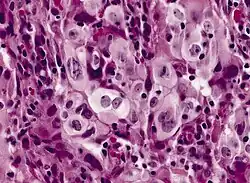

Adenokarzinom

_adenocarcinoma_of_the_lung.jpg)

Bis zu 20 Prozent der Lungenkarzinome sind Adenokarzinome. Sie entstehen aus schleimproduzierenden Zellen und entwickeln sich bevorzugt in Narbengewebe (z. B. alter Tuberkulose). Der Tumor liegt meist in der peripheren Lunge. Auch hier ist eine frühe Metastasierung typisch, die sowohl über die Lymphbahnen als auch über die Blutbahn erfolgt, und zwar bevorzugt in das Gehirn, die Leber und die Nebennierenrinde. Histologisch sieht man vor allem Drüsenformationen. Eine besondere Rolle spielt das vergleichsweise seltene bronchioloalveoläre Karzinom. Diese Sonderform, die ungefähr ein bis neun Prozent der untersuchten Bronchialkarzinome ausmacht, wächst langsam und innerhalb der anatomischen Strukturen. Radiologisch wird sie deshalb häufig mit einer Pneumonie verwechselt. Im Gegensatz zu anderen Bronchialkarzinomen besteht anscheinend kein ursächlicher Zusammenhang zu inhalativen Noxen.

Histologisch sollten je nach Subtyp drüsige, papilläre oder auch solide atypische epitheliale Strukturen mit Zeichen einer Schleimbildung zu sehen sein. Immunhistochemisch sind Adenokarzinome meist positiv für CK7 und negativ für Plattenepithelmarker wie CK5/6 und p63. Die Wachstumsrate (Ki-67) ist deutlich erhöht, aber nicht so stark wie beim SCLC. Der Nachweis von TTF1 spricht für ein in der Lunge entstandenes Adenokarzinom (DD Metastase eines Schilddrüsenkarzinoms). Bei Verdacht auf Vorliegen einer Metastase oder eines die Lunge infiltrierenden malignen Pleuramesothelioms können weitere Marker zum Einsatz kommen, um die Lokalisation des Primärtumors näher einzugrenzen.